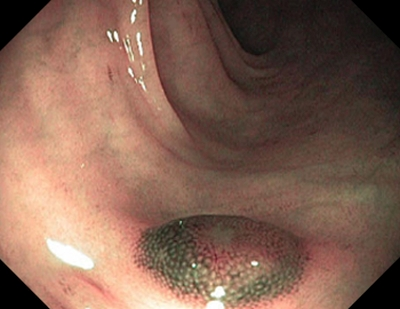

2 тип — характерний для аденоми

Колір: темніший (коричневіший), ніж навколишні

Судини: світліша ділянка в центрі, оточена більш товстими коричневими судинами

Поверхня: овальна, трубчаста, звивиста — наявність трубочок, лінійних або пучкових, світла ділянка в центрі, оточена коричневими судинами